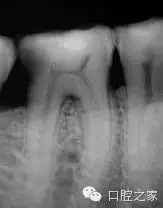

近中根的形態(tài)與頰舌方向的寬度使得我們必須考慮到根管間的交通與峽部(圖4)。峽部(吻合)的定義是牙髓間的通道,在同一個牙根內(nèi)連接兩個或者更多個根管。在年輕患者身上,我們會期望發(fā)現(xiàn)較粗的根管,同時具有較寬的峽部。繼發(fā)性牙本質(zhì)的沉積貫穿于牙齒的整個發(fā)育成熟過程,這些大的交通被逐漸分割為小的交通,直到最后,在40歲以后這些交通出現(xiàn)的頻率會逐漸降低。

在文獻所回顧的1,615顆下頜第一磨牙當中,50%的近中根和20%的遠中根中會出現(xiàn)V型的峽部。V型峽部被認為是兩個主根管之間真實的交通,或組織間的寬交通。因此,峽部的存在應當被認為是一種常規(guī),而不僅僅是診治年輕下頜第一磨牙時的例外。

在牙髓治療過程中,正是因為考慮到這些不可進入空間的消毒滅菌較為困難,我們應當將努力集中于提高根管化學沖洗的效能,利用目前我們所能獲得有效的根管沖洗系統(tǒng)。近期Von Arx指出峽部的識別、治療與消毒具有重要臨床意義;Von Arx發(fā)現(xiàn)在根管治療失敗需要進行根尖手術(shù)的病例中,有29%的病例存在完整的交叉吻合。